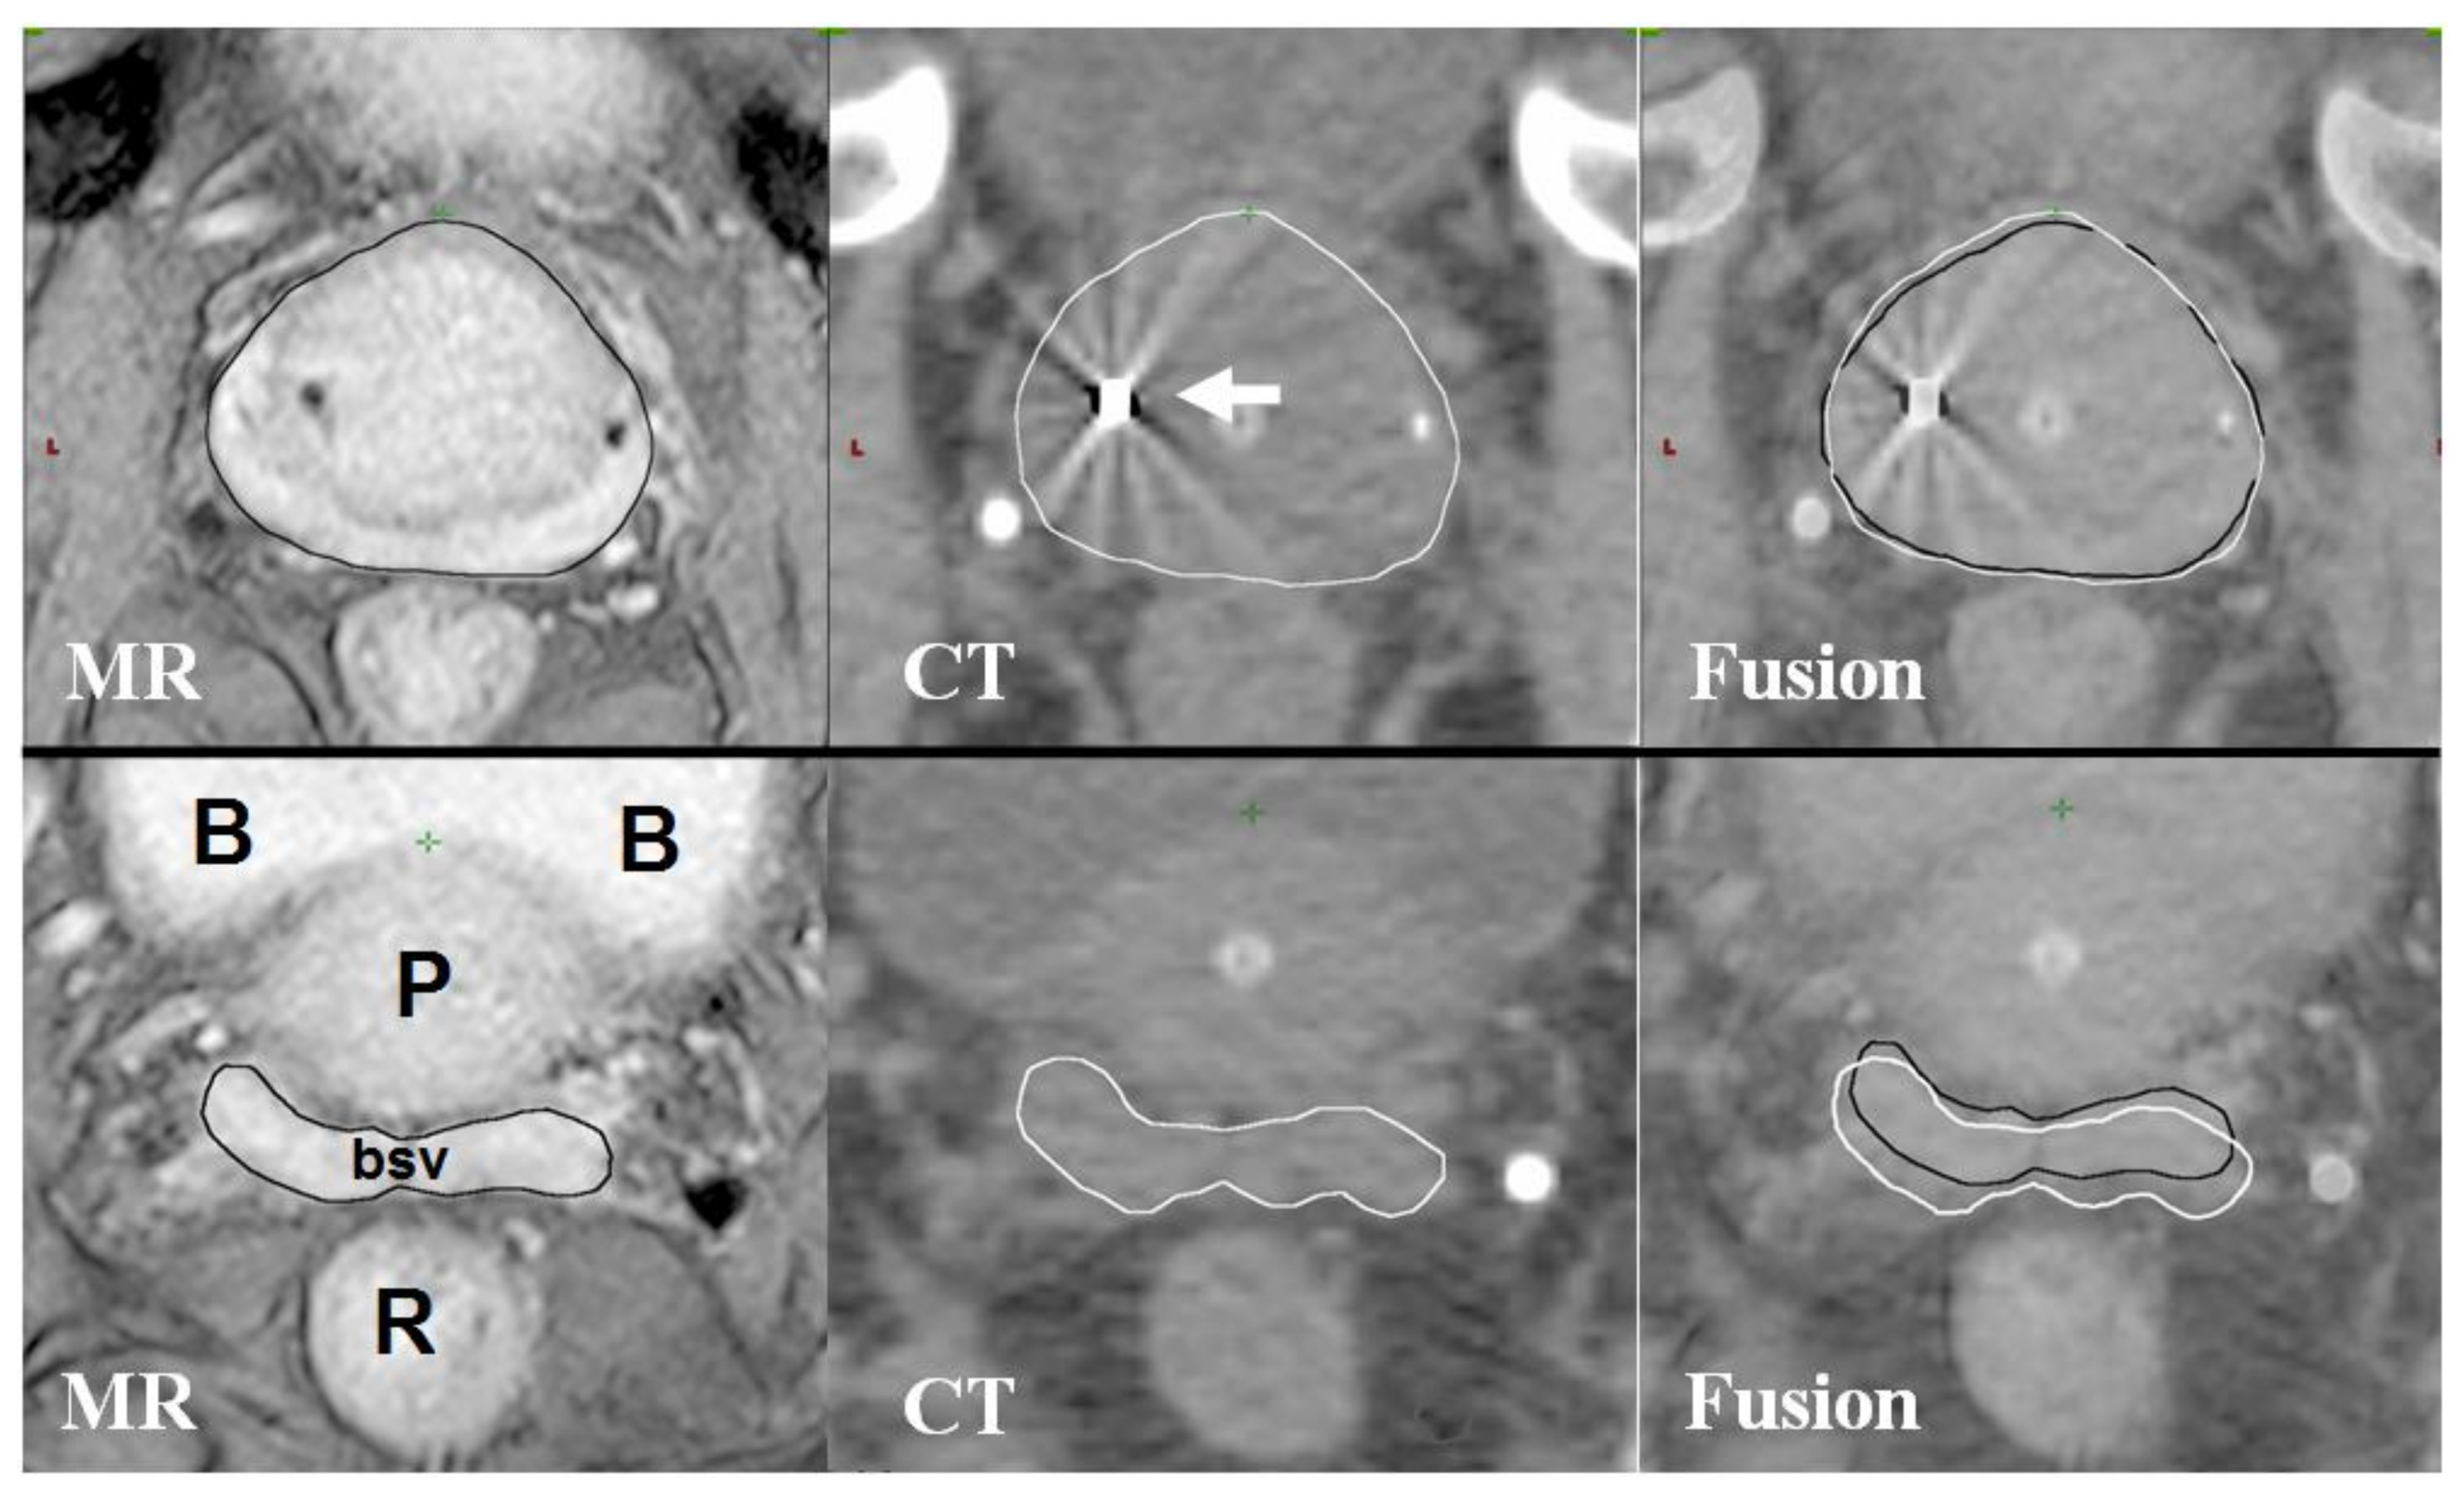

- Hentschel, B.; Oehler, W.; Strauss, D.; Ulrich, A.; Malich, A. Definition of the ctv prostate in ct and mri by using ct-mri image fusion in imrt planning for prostate cancer. Strahlenther. Onkol. 2011, 187, 183–190. [Google Scholar] [CrossRef] [PubMed]

- Debois, M.; Oyen, R.; Maes, F.; Verswijvel, G.; Gatti, G.; Bosmans, H.; Feron, M.; Bellon, E.; Kutcher, G.; Van Poppel, H.; et al. The contribution of magnetic resonance imaging to the three-dimensional treatment planning of localized prostate cancer. Int. J. Radiat. Oncol. Biol. Phys. 1999, 45, 857–865. [Google Scholar] [CrossRef]

- Sannazzari, G.L.; Ragona, R.; Ruo Redda, M.G.; Giglioli, F.R.; Isolato, G.; Guarneri, A. Ct-mri image fusion for delineation of volumes in three-dimensional conformal radiation therapy in the treatment of localized prostate cancer. Br. J. Radiol. 2002, 75, 603–607. [Google Scholar] [CrossRef] [PubMed]

- Parker, C.C.; Damyanovich, A.; Haycocks, T.; Haider, M.; Bayley, A.; Catton, C.N. Magnetic resonance imaging in the radiation treatment planning of localized prostate cancer using intra-prostatic fiducial markers for computed tomography co-registration. Radiother. Oncol. 2003, 66, 217–224. [Google Scholar] [CrossRef]